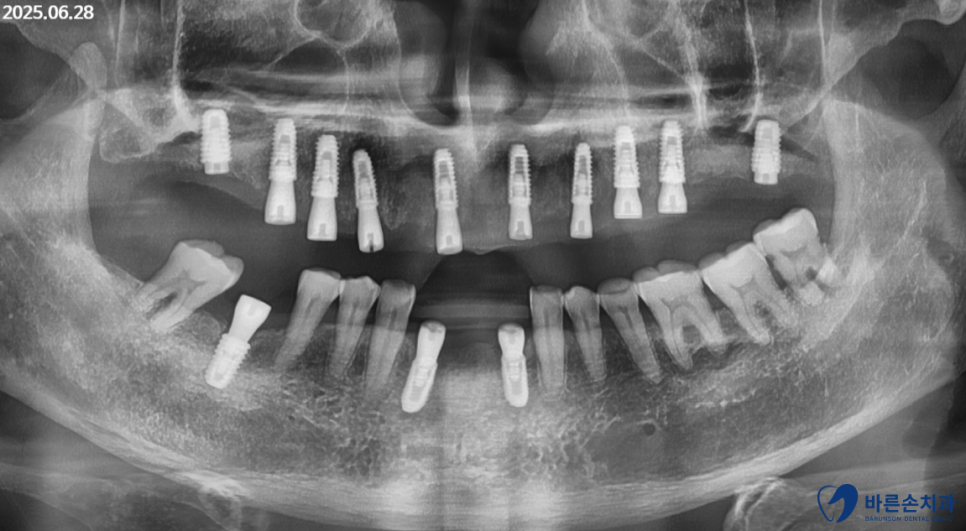

파노라마 엑스레이 촬영을 합니다.

사진을 보면 위에 치아는 전부 빠지고 뿌리만 3조각 남아있는 상태입니다.

아래는 앞니가 많이 흔들리는 상태이고 어금니도 하나가 상실되었네요.

남아있는 뿌리와 아래 앞니는 발치, 임플란트 하기로 하고

상실된 어금니 하나도 임플란트 하기로 계획했습니다.

임플란트 뿌리 식립 후,

2~3개월의 시간을 기다린 후

보철을 올립니다.

현재

그 기간동안 임시틀니를 사용하시고 계십니다.

곧 보철물이 이쁘게 올라갈 것 같네요~^^